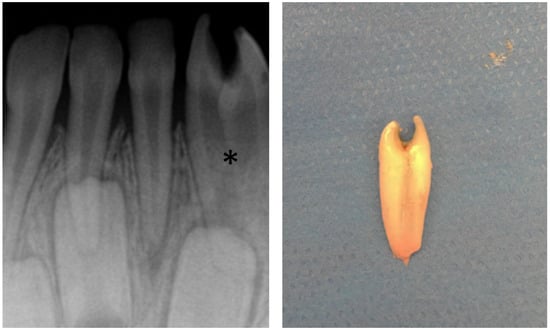

3.5.2. Dental Decay Radiologic Correlations

3.5.4. Periodontal Disease Radiologic Correlations